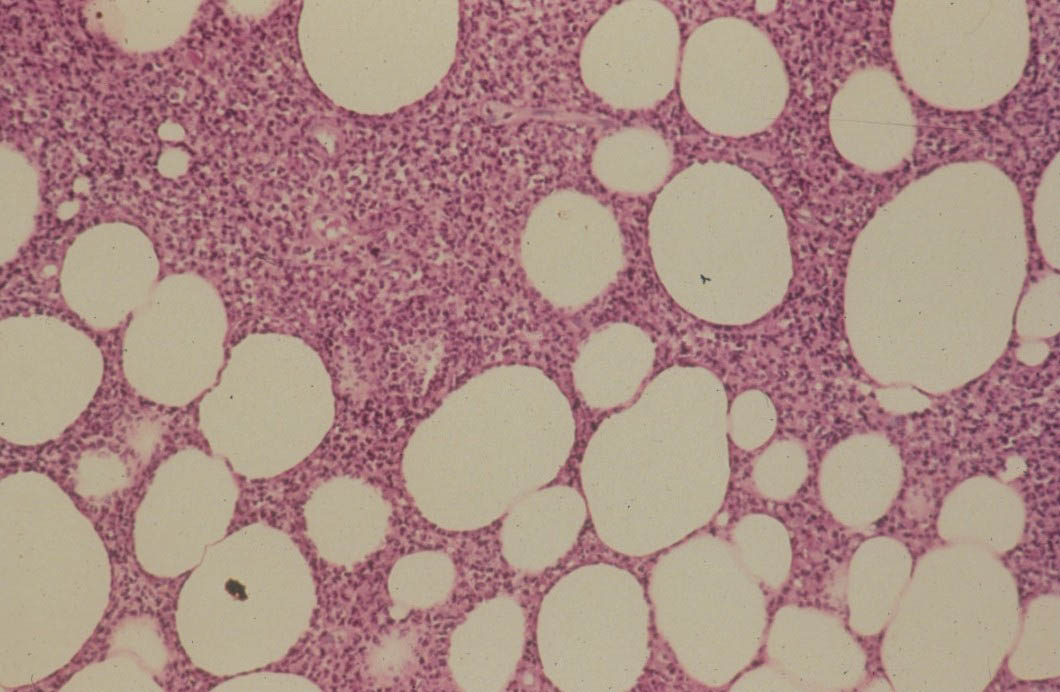

Atlas of skin histopathology

Panniculitis = التهاب السبلة الشحمية